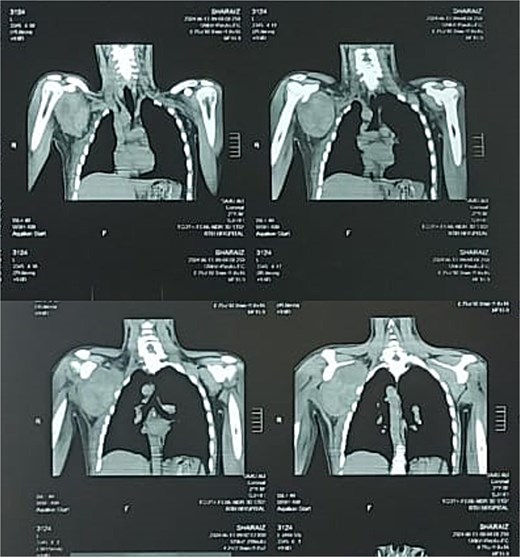

On palpation, the swelling was tender to touch and passive movements were also limited due to pain and swelling. Pain levels were recorded using a numerical rating scale (NRS), ranging from 0 (no pain) to 10 (worst pain imaginable) and was recorded at 7. Initially, a provisional diagnosis of scapulothoracic dissociation was made and computed tomography (CT) scan was advised. This revealed a large lobulated hematoma in the subscapularis muscle, as shown in the coronal plain CT image (Fig. 1).

Preoperative coronal plain CT image showing the subscapularis muscle hematoma.

The CT scan showed a larger well defined lobulated hematoma (8.9 × 8.5 × 11.5 cm) in the subscapularis including fluid levels representing hemorrhage. The deltoid showed a smaller hematoma measuring 1.8 × 1.6 × 2.1 cm. Preoperative and postoperative laboratory findings are summarized in Table 2. The patient did not report any co-morbidities or anticoagulative use.